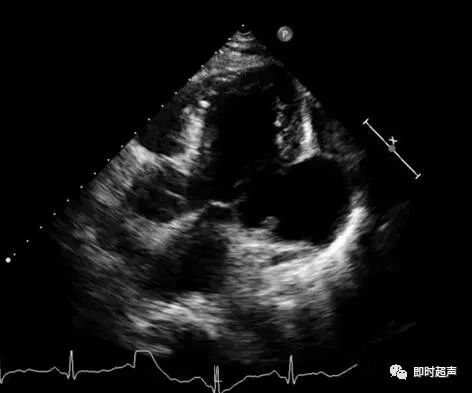

室壁瘤彩超图片,室壁瘤超声图片

室壁瘤破裂,经典!

心梗后室壁瘤还有假如何识别和诊断

一般情况尚可,但发现心脏确实发生重构,左室扩大,心尖形成室壁瘤

心梗后室壁瘤形成并室间隔穿孔

围手术期间,患者病情加重,复查心脏彩超示:ef40%,并可见左室后侧壁

室壁瘤超声图片

心脏室壁瘤超声图片

室壁瘤超声

室壁瘤

心室壁瘤

心尖室壁瘤